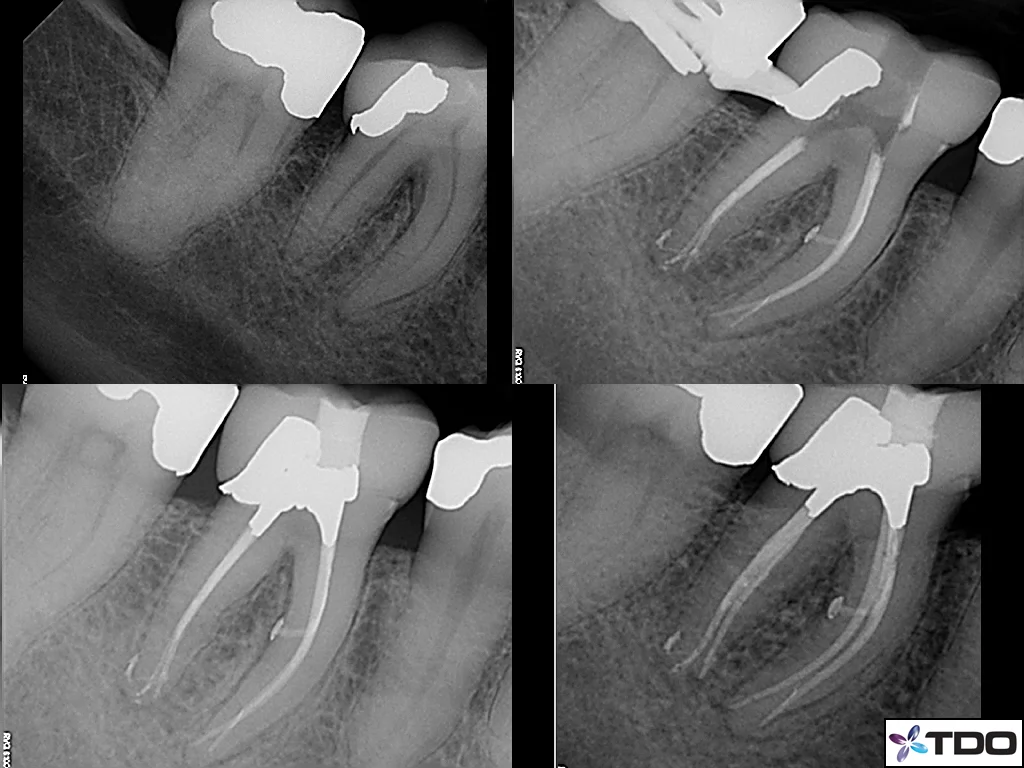

Minimally Invasive Endodontics (MIE):

This recently coined term refers to a concept of providing endodontic therapy while maintaining the maximal amount of tooth structure. Traditionally, dentists and endodontists were trained to open the roof of the tooth chamber to provide "straight line access" to all canals - which can significantly weaken the tooth. This was necessary prior to the advent of the modern endodontic armamentarium. The improved visualization and ergonomics provided by the microscope and the flexibility of today's rotary endodontic files allows us complete ideal endodontic therapy while minimizing the amount to coronal tooth structure removal. This minimalist idea can be extended to the root canals themselves. Most recent endodontic literature has been geared toward a "bigger is better" idea of cleaning and shaping. While there is little doubt that this methodology will lead to a "cleaner" canal, what is less clear is whether this "increased cleanliness" improves the long-term success. Interesting, endodontic success rates have not risen significantly in recent years. This would at least raise the possibility that "bigger/cleaner" may not matter in the way that we have been trained. Our goal is simply to treat the patient's symptoms/disease while respecting the dentin (especially the pericervical dentin). This method does not create "the look" of the dramatically tapered root canal preparations that are seen in most of today's endodontic marketing material; however, it should lead to improved long-term success and tooth retention. The cases below illustrate how this concept has been implemented into our practice.